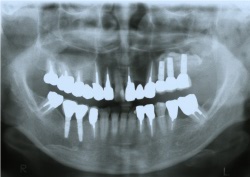

●上顎洞までの距離が短く、このままではインプラントができません。

●インプラント周囲に骨を作る事によって、インプラントができます。